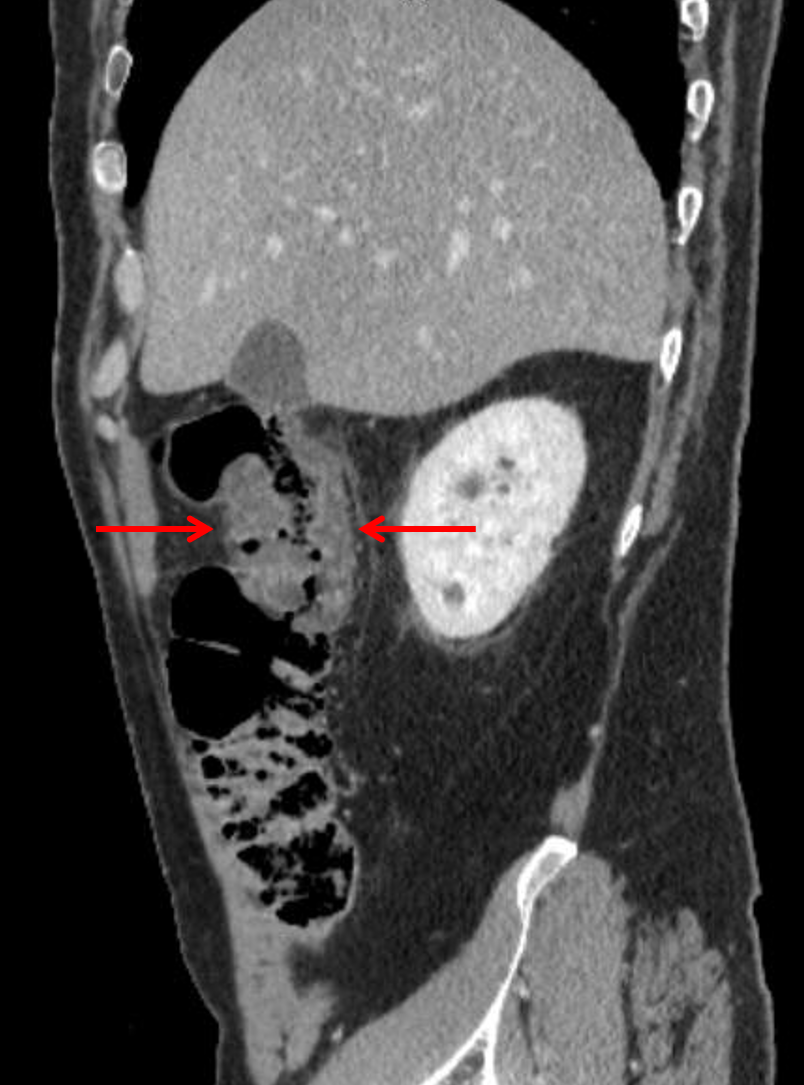

Age: 60

Sex: Male

Indication: Right upper quadrant pain

Sample ReportFocal colitis involving the hepatic flexure, which may relate to an infectious (including C. difficile) or inflammatory source. Recommend correlation with age-appropriate screening colonoscopy to exclude underlying neoplasm.

Multiple pulmonary nodules with the largest measuring 5 mm in the left lower lobe. Recommend nonemergent chest CT for further evaluation.

Hepatic steatosis.